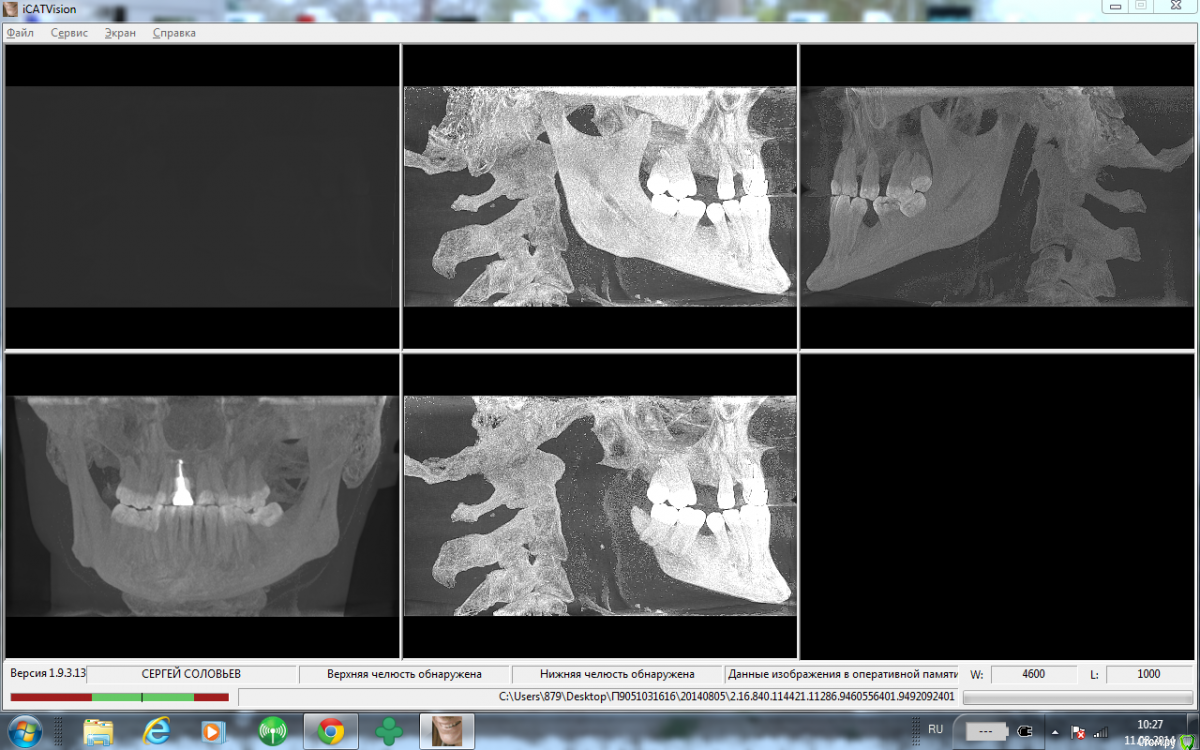

St. Опубликовано 3 февраля, 2016 Поделиться Опубликовано 3 февраля, 2016 Вот скрины области 34-37 http://s017.radikal.ru/i422/1602/29/827509a5e8b7.jpghttp://s020.radikal.ru/i715/1602/79/8ae3b175009f.jpghttp://s019.radikal.ru/i642/1602/df/6069a3f8c407.jpghttp://s020.radikal.ru/i708/1602/27/32fb4607230f.jpghttp://s019.radikal.ru/i618/1602/5b/21d7f2ba2d62.jpghttp://s019.radikal.ru/i619/1602/de/2eb04456028f.jpghttp://s010.radikal.ru/i311/1602/bd/f4a561bc6c1f.jpghttp://s017.radikal.ru/i414/1602/57/97d820fac3da.jpg Ссылка на комментарий